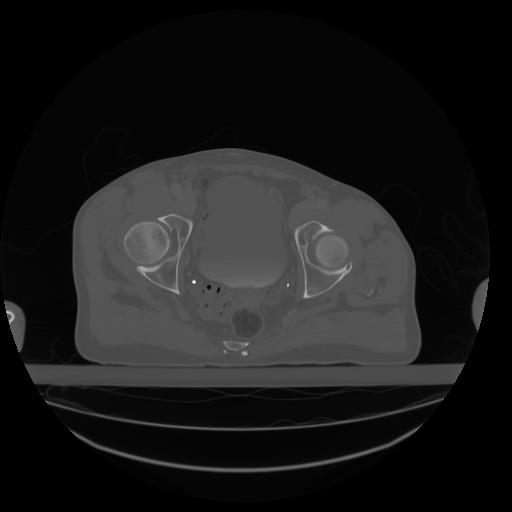

27 CUERPO,CE,Axial,3.0,CUERPO,,